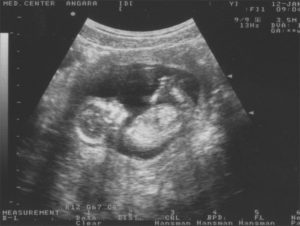

УЗИ на 13 неделе беременности

УЗИ на 13 акушерской неделе беременности назначается при постановке на учет в женской консультации. В этот срок узист будет смотреть правильно ли расположена плацента, прослушает частоту сердцебиения эмбриона, проконтролирует, достаточно ли высока двигательная активность плода.

Сейчас на ультразвуковом исследовании определяется воротниковая зона. Ведь это важный показатель для выявления генетических аномалий.

Для диагностики истмико-цервикальной недостаточности проводится осмотр состояния маточного зева.

Как правило, первый скрининг проводят на 12 неделе беременности, но если по каким-то причинам женщина не смогла это сделать, то его переносят на 13 неделю. Важно пройти это исследование до окончания I триместра, ведь скрининг способен выявить возможные риски развития плода, поэтому пренебрегать им не стоит.

В рамках скрининга проводится первое ультразвуковое исследование, если до этого беременность протекала без осложнений. Такая процедура позволяет впервые увидеть малыша. Кроме того, УЗИ определяет:

- жизненные показатели плода,

- работу сердца эмбриона,

- возможные патологии и пороки,

- размеры и развитие малыша.

На УЗИ также уже могут предположительно назвать пол ребенка.

Если к этому времени беременность протекала без осложнений, то, возможно, на 13 неделе состоится ваше первое УЗИ. Вы сможете видеть, как бьется сердечко маленького, как он двигается, а врачу исследование даст возможность оценить состояние плода и беременности:

- точно установить срок беременности и количество плодов;

- оценить жизненные показатели плода;

- определить наличие/отсутствие тяжелых пороков, несовместимых с жизнью;

- провести скрининговое исследование на определение группы риска женщины относительно хромосомных аномалий у плода (в частности, синдрома Дауна).